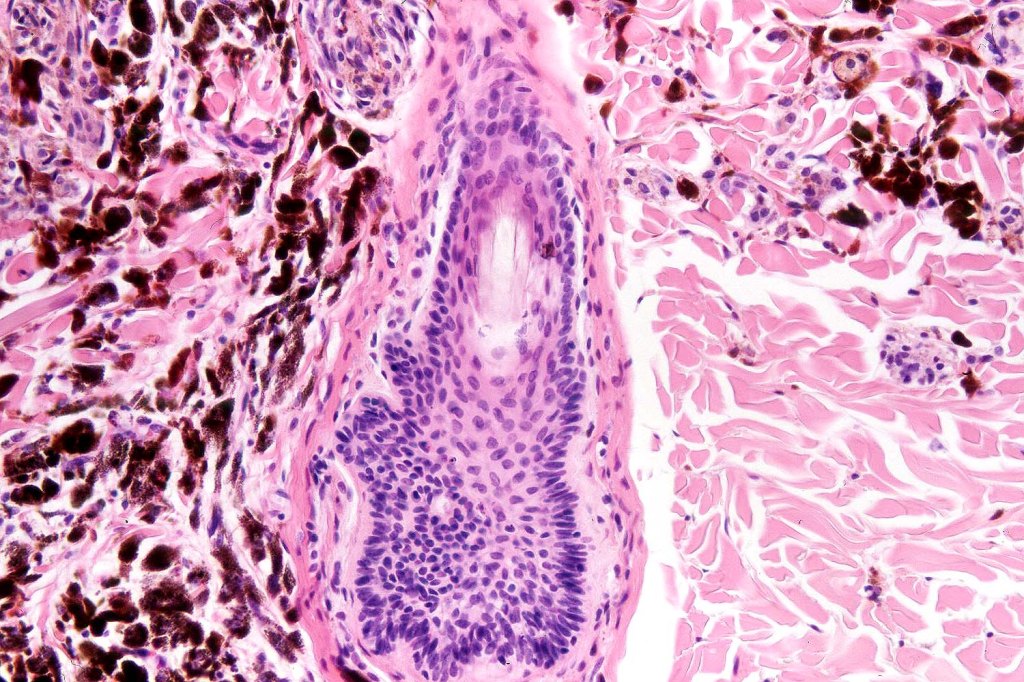

Combined common melanocytic nevus & BAP1-inactivated melanocytoma